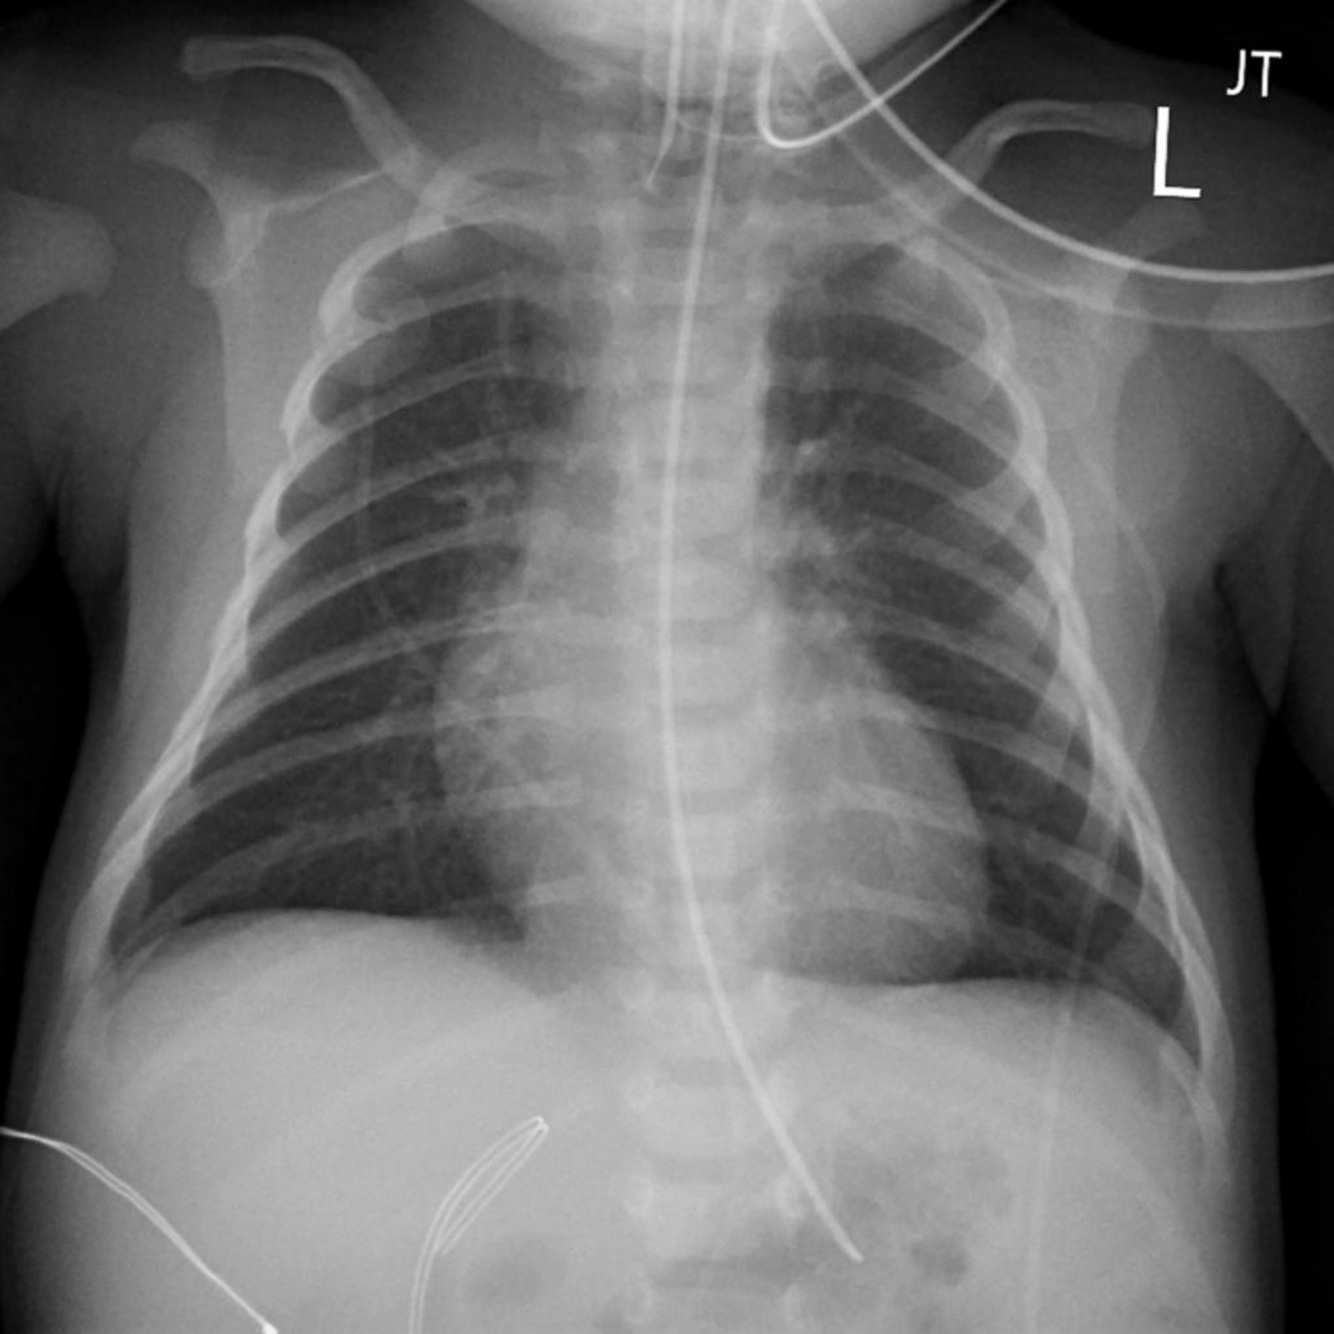

right pleural effusion shown on x-ray,